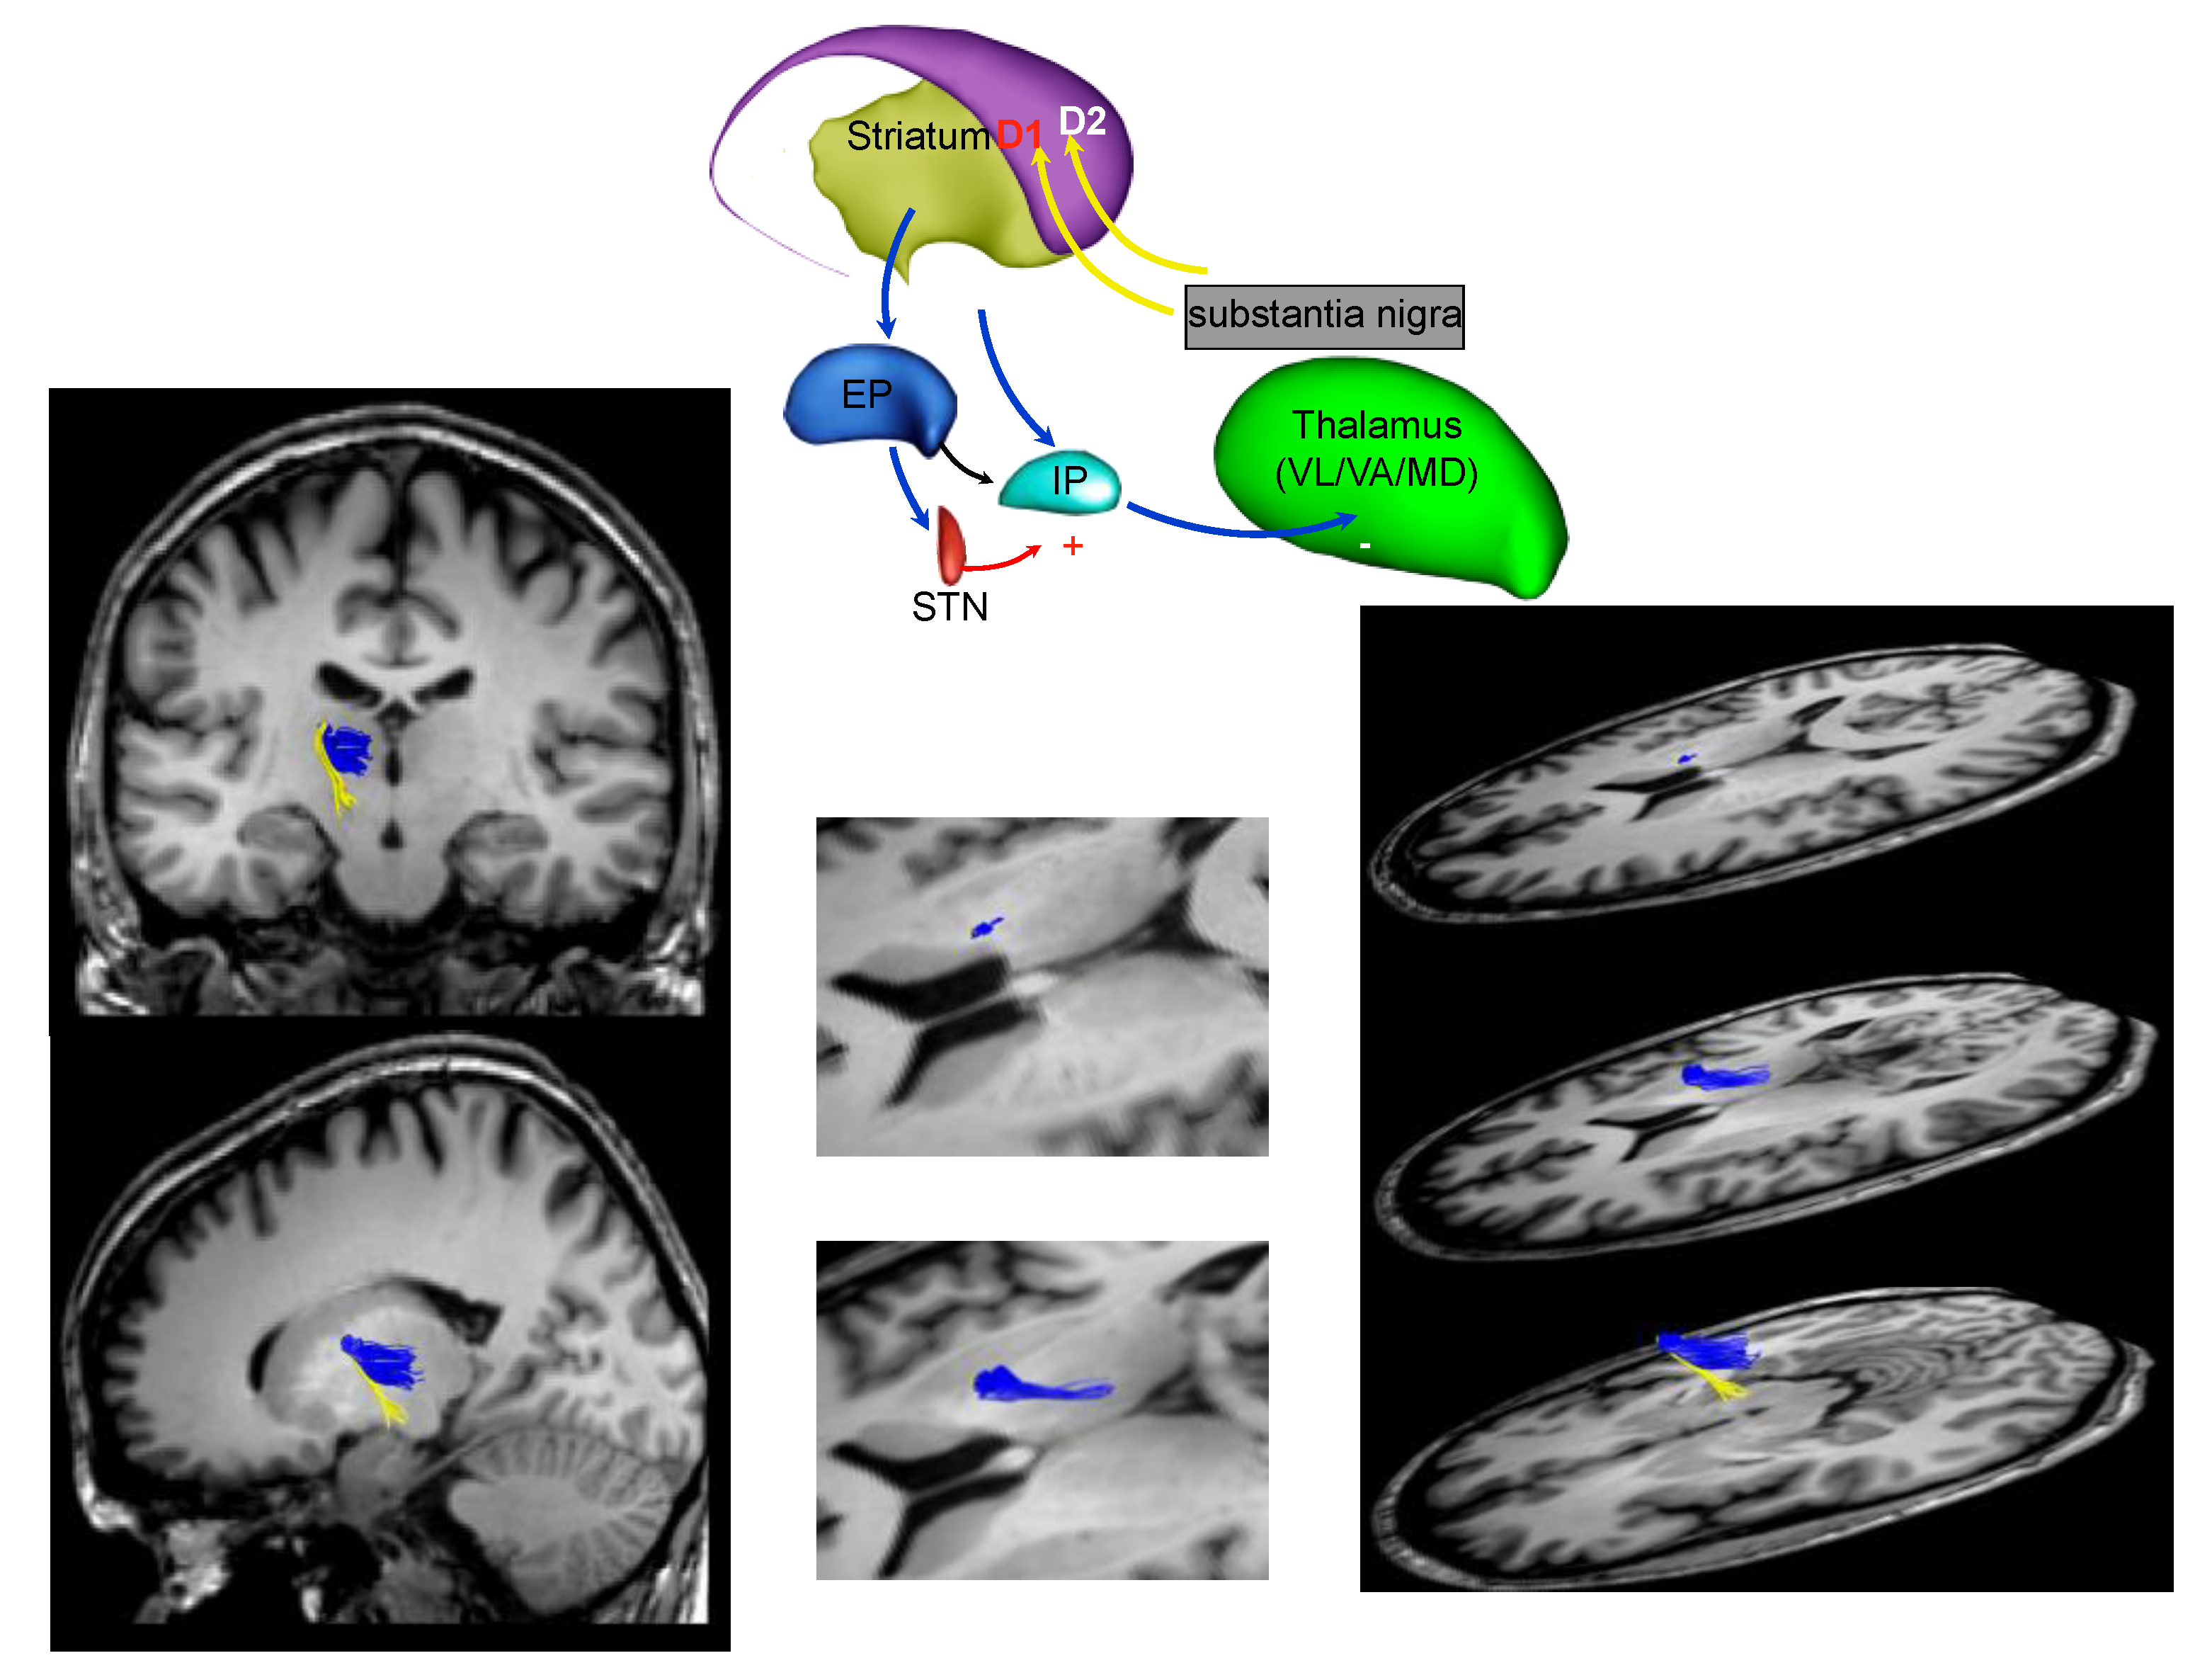

3. Parkinson’s Disease Subtypes Identified by Tractography